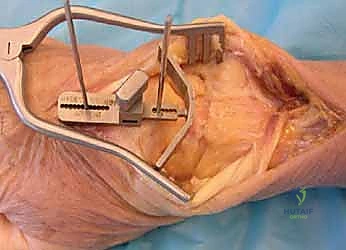

A longitudinal dorsal incision, positioned slightly radial to the midline, is made extending from approximately 4 cm proximal to the radiocarpal joint down to the midpoint of the third metacarpal shaft. Sharp dissection is carried down through the subcutaneous tissues to the level of the extensor retinaculum, taking meticulous care to identify and protect the sensory branches of the superficial radial nerve and the dorsal sensory branch of the ulnar nerve. The third dorsal compartment is opened, and the extensor pollicis longus (EPL) tendon is exposed, mobilized, and retracted radially. The retinaculum is then elevated as a continuous flap. The radial wrist extensors (ECRL and ECRB) are exposed and mobilized radially, while the first compartment tendons are mobilized from the distal radius and protected. The tendons of the fourth and fifth compartments are mobilized ulnarly, ideally without opening their respective synovial compartments to prevent postoperative adhesions.

With the extensor tendons mobilized and safely retracted, a longitudinally based capsulotomy is performed. The capsule is reflected as radially and ulnarly based full-thickness flaps, exposing the distal radius and the entire carpus down to the base of the third metacarpal. Preparation of the distal radius involves scoring a reference line to ensure the DRUJ is preserved. The radial canal is sequentially broached to accept the modular radial stem. The modular radial stem component is designed to fill the distal radius canal to prevent loosening and provide rotational stability. While approved for implantation with bone cement (PMMA), most modern wrists are implanted with press-fit, cementless fixation to encourage osteointegration. Cement is generally reserved for cases of significantly compromised bone stock, severe osteopenia, or revision scenarios.

Following capitate reaming, the chosen carpal plate and stem are assembled and inserted into the capitate and seated onto the resected carpal surface. The carpal plate is anchored to the carpus with a radial screw that optimally does not penetrate the second metacarpal, and a second screw placed ulnarly into the hamate. This construct ensures stable distal fixation while avoiding the deleterious lever arm of a long metacarpal stem. Trial reductions are performed to assess stability, range of motion, and impingement. Once kinematics are confirmed, the definitive ultra-high-molecular-weight polyethylene (UHMWPE) body—which is direct compression molded onto a cobalt chrome alloy radial body—is impacted. The capsule and extensor retinaculum are meticulously repaired to prevent extensor tendon bowstringing and provide a robust soft tissue envelope over the implant.

Clinical & Radiographic Imaging Archive